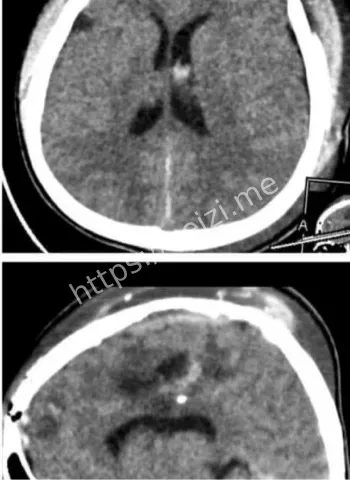

金边坤塔帕花儿童医院10月8日上演医学奇迹,一颗意外射入儿童大脑的气枪金属子弹被成功取出,手术用德国蔡司显微镜辅助,历时8小时止血止损。这起脑损伤事件引发热议,小患者恢复中,凸显儿科医疗前沿技术与医护团队的无畏精神,守护儿童生命安全。

话说回来,这颗子弹是怎么射进去的?哎,八卦起来总得挖挖根儿啊!据说这是个意外,孩子可能在附近玩气枪游戏,或者大人不小心操作失误,结果这玩意儿就钻进了小脑袋。气枪这东西,看起来像玩具,威力却不小,尤其是对小孩儿,头部中弹直接就是脑损伤大麻烦。金边这地方,热带气候,孩子们爱在户外疯玩,但安全教育跟不上,类似意外时有耳闻。这次事件一出,大家都开始反思:家长们得多盯着点啊,别让好奇心变成灾难。医院那边也没闲着,术前他们得先做一堆检查,CT、MRI啥的,全方位扫描,确保手术路径最安全。

哇塞,高科技这时候就闪亮登场了!坤塔帕花儿童医院这次牛就牛在用了德国最新一代的蔡司显微镜,这玩意儿放大倍数高到能看清脑神经末梢,手术精度直逼毫米级。8小时里,医生们通过这镜子,避开血管和重要脑区,一点点剥离子弹周围的组织。别小看这设备,它不光帮着看清,还能实时监控出血情况,避免二次损伤。说白了,这技术让儿童脑手术从“盲人摸象”变成“高清直播”,风险降了好几成。金边这家医院本就是儿科重镇,引进这种前沿玩意儿,简直是为东南亚小孩儿开了扇希望之窗。